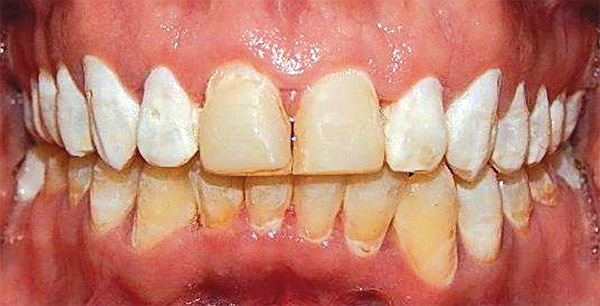

Respecto a los estudios finales intraorales, en las fotografías podemos observar la coincidencia de líneas medias dentales (Figura 19), la clase I molar y canina bilateral (Figura 20 y 21).

Finalizado el tratamiento se realizaron carillas provisionales en el maxilar superior de los diente 15, 14, 13, 12, 11, 21, 22, 23, 24, 25 para su posterior rehabilitación (Figura 22) el overjet y overbite adecuado.

En la vista oclusal podemos ver la corrección del apiñamiento superior e inferior y las adecuadas formas de arco (Figura 23).

El tiempo total del tratamiento fue de un 1 y 8 meses, se lograron los objetivos planteados: se eliminar las manchas, se mejoró el color de los dientes. Se hizo la expansión dentoalveolar superior, Se preparó la superficie dental para el bondeo de brackets, se corrigió el apiñamiento maxilar y mandibular, se obtuvo la clase I canina y molar bilateral. Las líneas medias dentales coinciden, el overbite y overjet mejoró (Figura 25).

Respecto a la corrección de la sonrisa del paciente (Figura 26), con la restauración de protésica, cabe señalar que los dientes con fluorosis grado 1 tienen un color muy blanco, motivo por el cual la resina no pudo igualar el color, pero con las carillas ya se asemejó la tonalidad de los dientes. Finalmente la estabilidad del postratamiento a cargo de un retenedor circunferencial con cinturón vestibular superior e inferior (Figura 27).